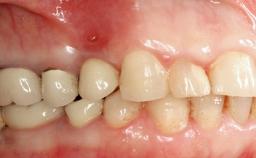

A 82-year-old female patient was referred to the Department of Oral Surgery and Stomatology at the University of Bern, Switzerland, for further diagnosis and treatment of growing discomfort in the right mandible (implant 45) and left maxilla (implant 23). The patient had had implants of various types inserted in the mandible and maxilla over the course of the previous three decades (in the 1980s and 1990s). The patient had received removable partial dentures on implants in the maxilla and on natural teeth in the mandible. The implants in the posterior right mandible had been restored with two splinted single crowns. The lower partial denture was not well tolerated by the patient and therefore had not been worn for over ten years. After insertion of the implants, there had been no complications for many years, but implants 45 and 46 as well as 23 had begun to exhibit signs of peri-implantitis with limited bone loss several years previously. The infection had been treated by the private practitioner, and bone loss around the three implants had not progressed until about half a year previously.